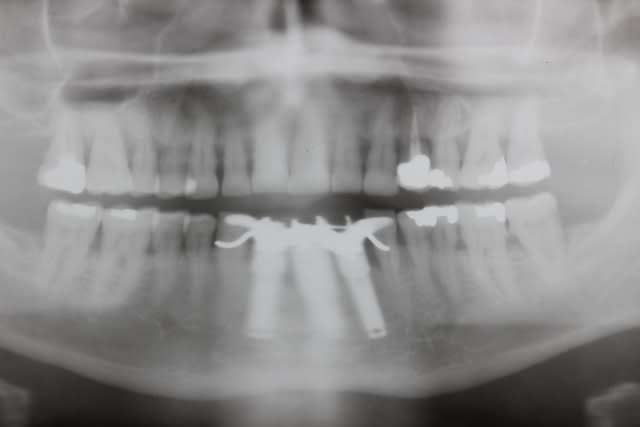

Le dentascan de la mandibule pour que vous compreniez mieux la difficulté...quais impossible de la considérer en cylindres même en déplaçant le NDI vous n avez aucune hauteur exploitable... Même des lame de Likow n y passent pas et les sous périostés sont interdits en Europe

J ai perdu mes deux foutus cylindres et ai dû les remplacer par deux double disk...et changer les deux mono disk du secteur droit

Et oui l implanto basale n est pas non plus un long fleuve tranquille